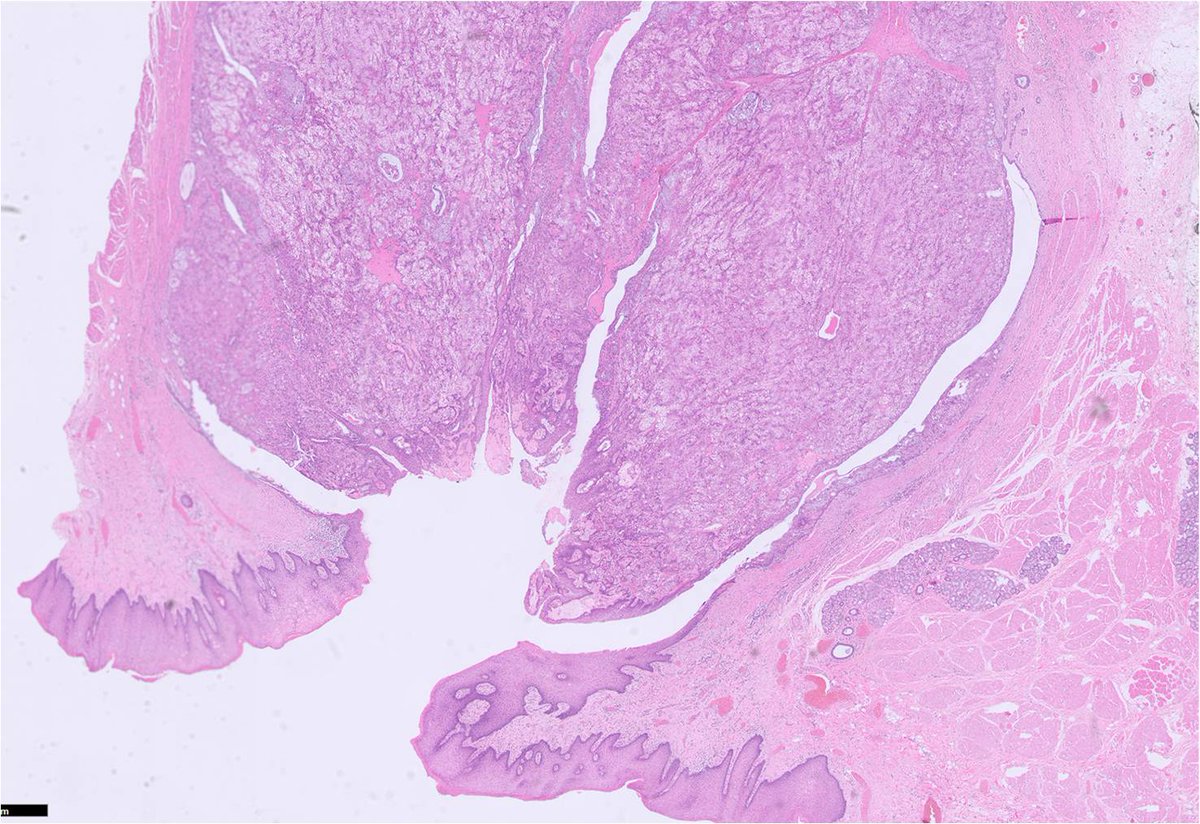

Section of a cemento-ossifying fibroma of the mandible. You won't find this under fibro-osseous lesions in the latest WHO classification; instead it's been grouped under 'benign mesenchymal odontogenic tumours' #oralpath #pathology #odontogenic